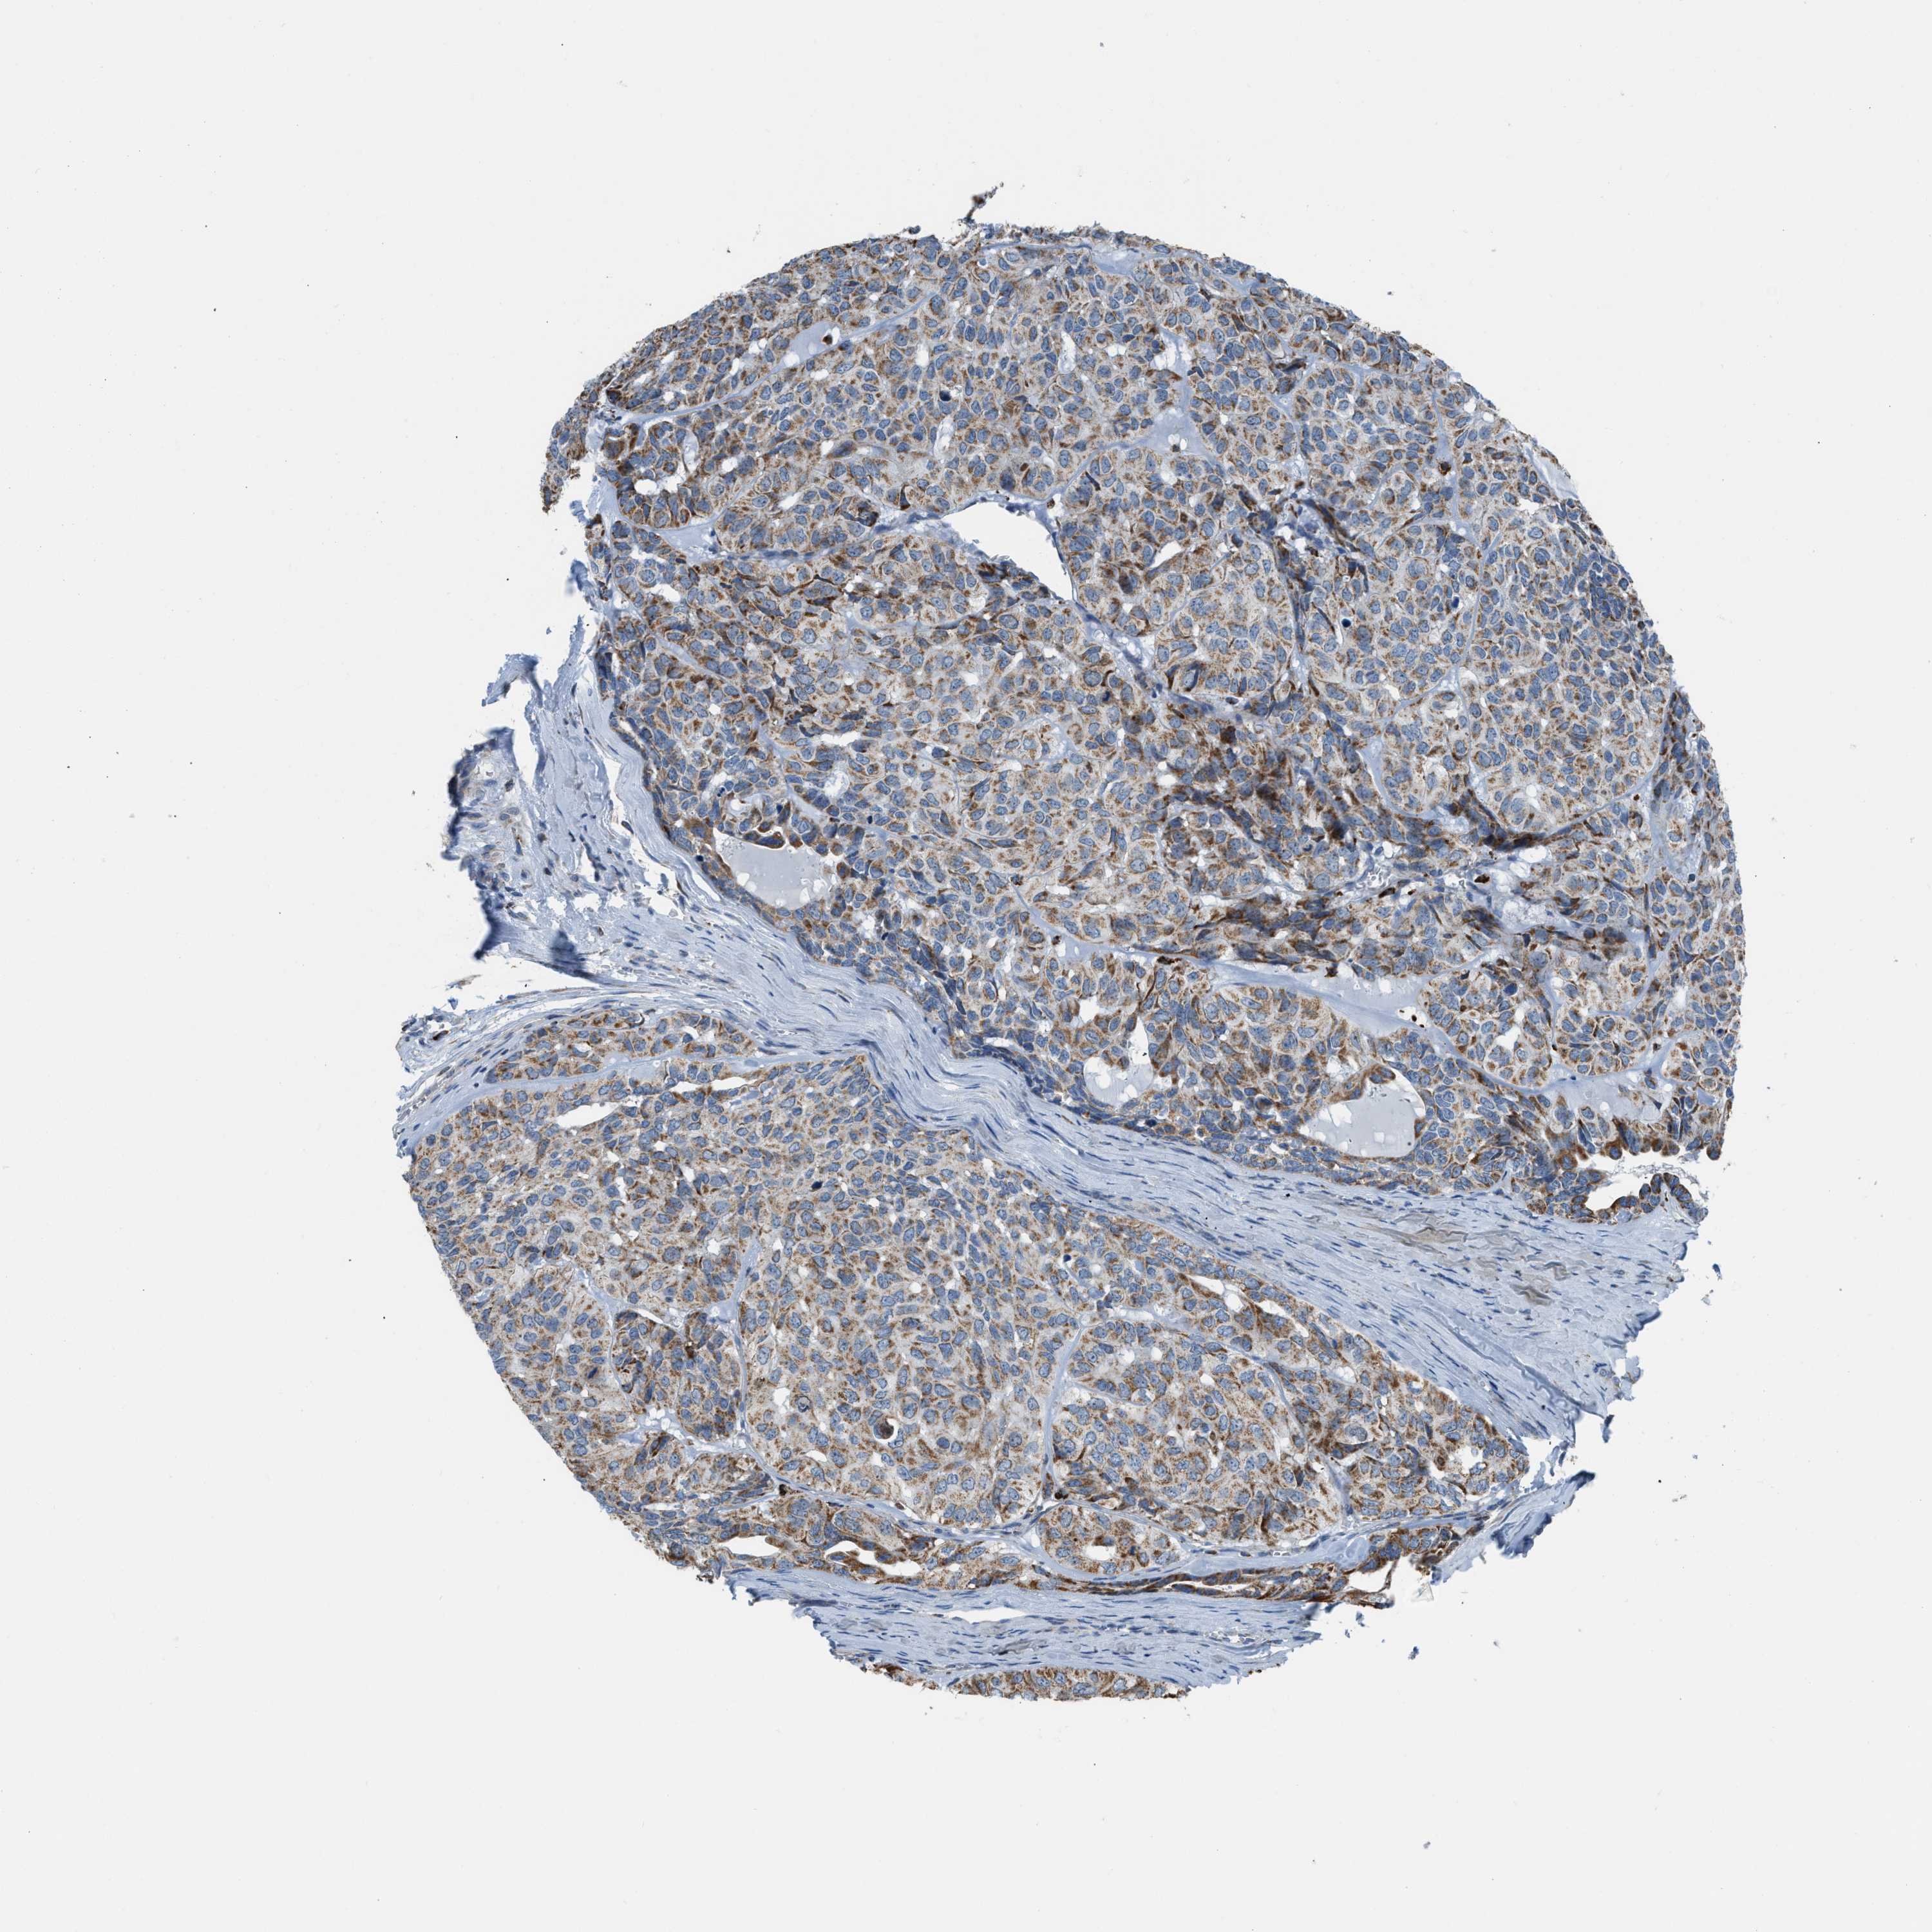

HEAD AND NECK CANCER - Protein expressioni

A mouse-over function shows sample information and annotation data. Click on an image to view it in a full screen mode. Samples can be filtered based on level of antibody staining by selecting one or several of the following categories: high, medium, low and not detected. The assay and annotation is described here.

Antibody stainingi

Antibody staining in the annotated cell types in the current human tissue is reported as not detected, low, medium, or high, based on conventional immunohistochemistry profiling in selected tissues. This score is based on the combination of the staining intensity and fraction of stained cells.

Each image is clickable and will lead to virtual microscopy that enables deeper exploration of all samples and also displays staining intensity scores, fraction scores and subcellular localization as well as patient and tissue information for each sample.

Antibody HPA016552

Staining

High

Medium

Low

Not detected

Intensity

Strong

Moderate

Weak

Negative

Quantity

>75%

75%-25%

<25%

None

Location

Nuclear

Cytoplasmic/membranous

Cytoplasmic/membranous,nuclear

Adenocarcinoma, NOS